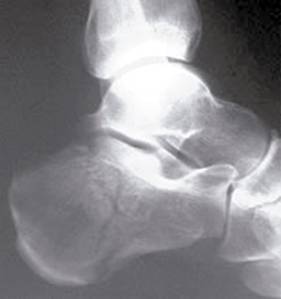

Por imagen, tres radiografías simples:

Rx lateral de pie y tobillo: determinamos el ángulo de Böhler (Figura 1), definido por la línea que une los puntos más altos de los procesos anterior y posterior medida en la radiografía lateral -es normalmente de 25-40o-; también el ángulo crucial de Gissane (Figura 2), que calcula la congruencia articular de la faceta posterior, medido entre la faceta posterior y el pico del calcáneo -es, de manera habitual, de 95-105o-.

Rx axial de calcáneo de Harris: ver ensanchamiento.

Rx dorsoplantar del pie: ver articulación calcaneocuboidea.

TAC (tomografía axial computada) de calcáneo: obligatoria en todas las fracturas intraarticulares o con sospecha de serlo.